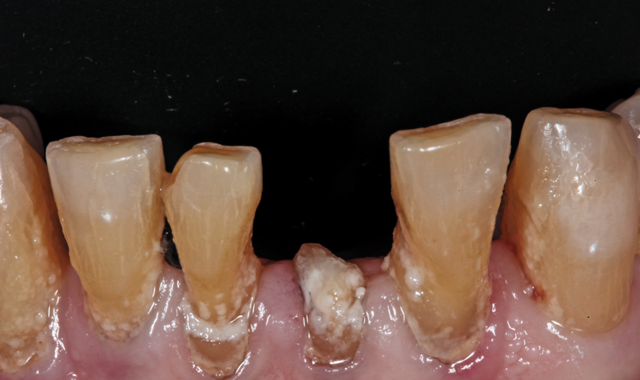

An 88-year-old man presented for restoration of tooth #25, which was fractured and had been endodontically treated (Fig. 1). A thorough intraoral and radiographic examination was performed, which revealed damage to the remaining anterior mandibular teeth incurred over the years as a result of scaling and curettage (Fig. 2). This damage to the

root surface of the lower incisors-which was visible on the radiograph (Fig. 3)-is known as “Riffle-ization.” Described by Dr. Riffle as a technique for removing every last bit of calculus during repeated root scaling, what is now known as “Riffle-izing," ultimately-over the years-changes the shape of the neck of the tooth to resemble an hour glass.